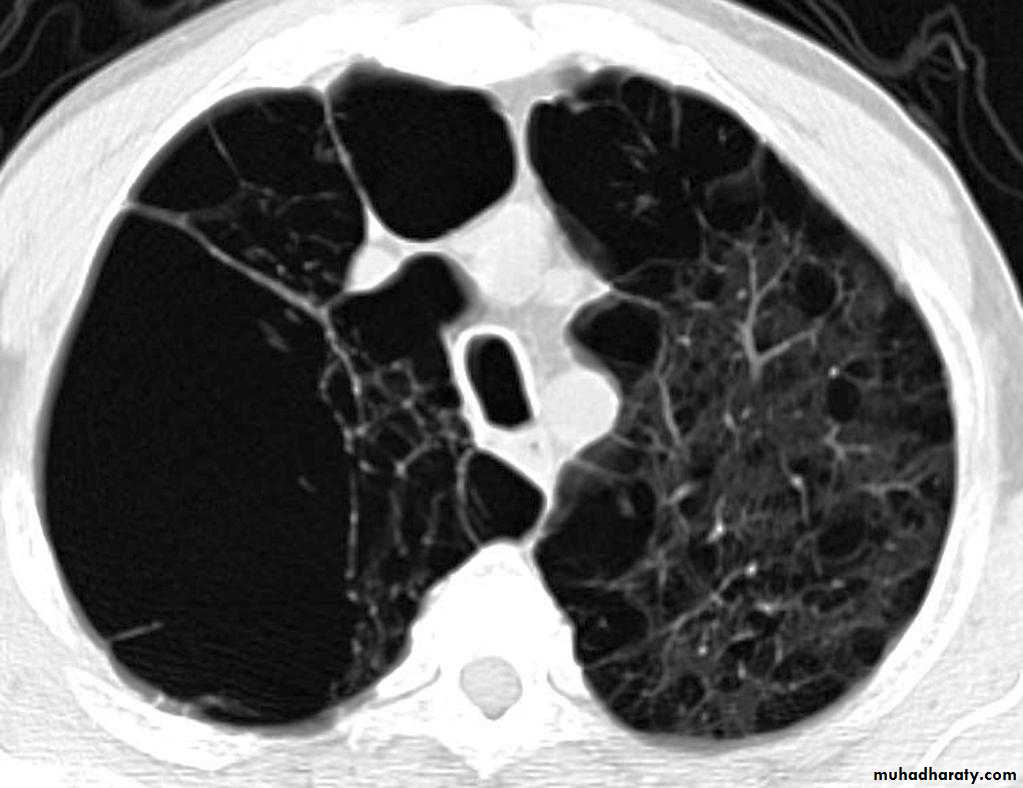

Bronchiectasis refers to abnormal dilatation of the bronchial tree and is seen in a variety of clinical settings. CT is the most accurate modality for diagnosis. It is largely considered irreversibleCauses of bronchiactasias very important to consider

Plain radiograph

1. Tram-track opacities are seen in cylindrical bronchiectasis, and

2. air-fluid levels may be seen in cystic bronchiectasis.

Honey comb shadow

3.Overall there appears to be an increase in bronchovascular markings, and bronchi seen end on may appear as ring shadows .

4.Pulmonary vasculature appears ill-defined, thought to represent peri bronchovascular fibrosis .